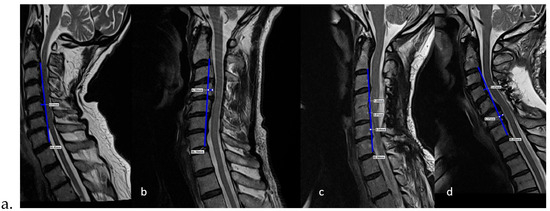

Background/Objectives: This case represents the successful treatment of cervical spine injury from high-speed rear-impact motor vehicle collision and abnormal cervical kyphosis with left arm radiculopathy, utilizing conservative spine care rehabilitation methods. This patient was treated with a multimodal treatment approach integrating a cervical spine extension traction protocol. Subject and Methods: A 50-year-old male with a history of motor vehicle collision presented with left arm radiculopathy, as well as cervical and upper thoracic spine pain. Notably the cervical spine presented with kyphotic deformity. The patient presented, after a being struck during a rear-end motor vehicle collision, with neck, upper back, and left arm radiculopathy. Prescription medication and traditional chiropractic care proved ineffective for substantive symptom and quality-of-life improvement. Treatment frequency was three times per week for eight weeks using the Chiropractic Biophysics® protocol of mirror image (MI®) postural exercise, spinal adjustment, and cervical spinal traction. On completion of in-office care, the patient was treated monthly, performed home care at least three times per week, and was re-examined at one year. Results: Final examination after eight weeks of care showed significant improvement in cervical lordosis (21.8 degrees), resulting in reduced cervical kyphosis. The patient completed outcome indices before, during, and 12 months after cessation of active care, all indicating improvement. Conclusions: This case report demonstrates both subjective and objective improvement in cervical spine kyphosis and attendant symptoms. The successful treatment of chronic pain, peripheral weakness, and radiculopathy with long-term follow-up using CBP care is documented as well. The treatment was designed to improve sagittal balance and reduce radiographic abnormalities evincing spinal misalignment. Administration of subjective, objective, and health-related quality-of-life outcome indices during, following, and 12 months post-treatment are suggestive of long-term efficacy of Chiropractic BioPhysics® (CBP) treatment methods. Larger studies are needed to substantiate this given the limitations of a case report. Full article

Background/Objectives: This case represents the successful treatment of cervical spine injury from high-speed rear-impact motor vehicle collision and abnormal cervical kyphosis with left arm radiculopathy, utilizing conservative spine care rehabilitation methods. This patient was treated with a multimodal treatment approach integrating a cervical [...] Read more.